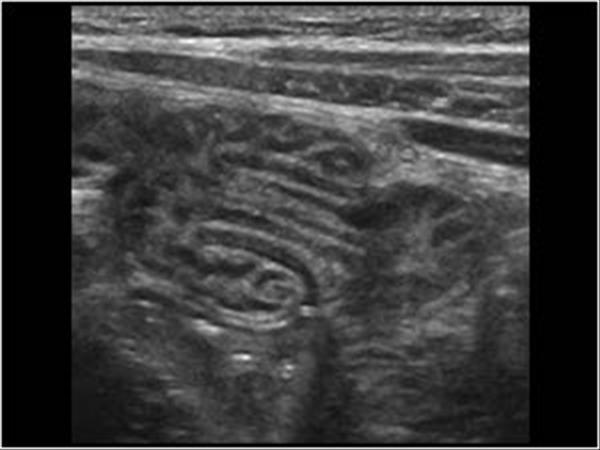

Ascariasis

infection of round worms

asymptomatic

biliary colic

cholangitis

Poor hygiene

Ascariasis

infection of round worms